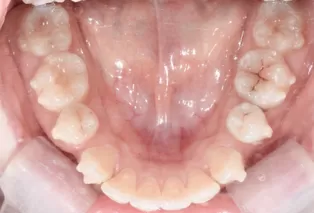

Intraoral photos